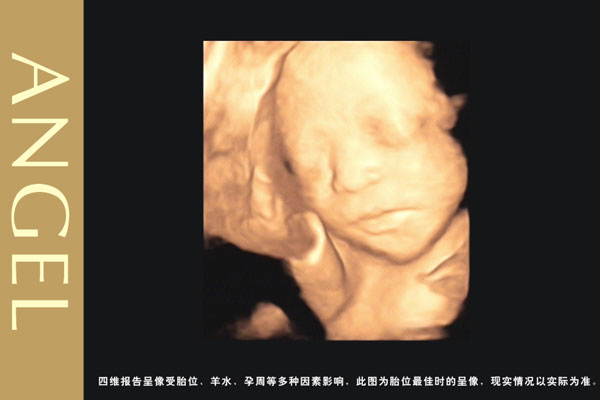

四维彩超和三维彩超有区别吗?三维彩超和四维彩超的区别就在于在一个“时间维”,也就是说,三维彩超是图片,四维彩超是录像,可以让孕妈妈看到胎儿一连串的动作。

四维彩超是动态的,三维彩超是静态的,所以四维看起来会更清楚明晰,三维彩超只能是某个时间点上的照片,四维彩超的就可以做成DV那样连续的,可以刻录光盘。三维彩超和高清四维彩超一样的有排畸的作用,高清四维彩超更加准确。